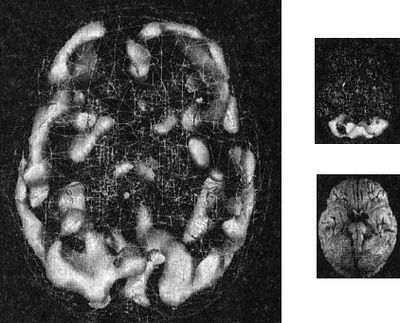

При предоставлении химиотерапии в то же время, что и лучевая терапия пациентам с локально прогрессирующим головным и шейным раком (кто не перенес операцию) более чем удваивает их выживание без событий к 2,2 годам, по сравнению с 1,0 годами с одной только лучевой терапией. Везде, где возможно, химиорадиация должна стать стандартом для всех пациентов с прогрессирующим головным и шейным раком, в которых хирургия не адекватна, приходит к заключению, что Статья издала Онлайн Сначала при Онкологии Скальпеля. …